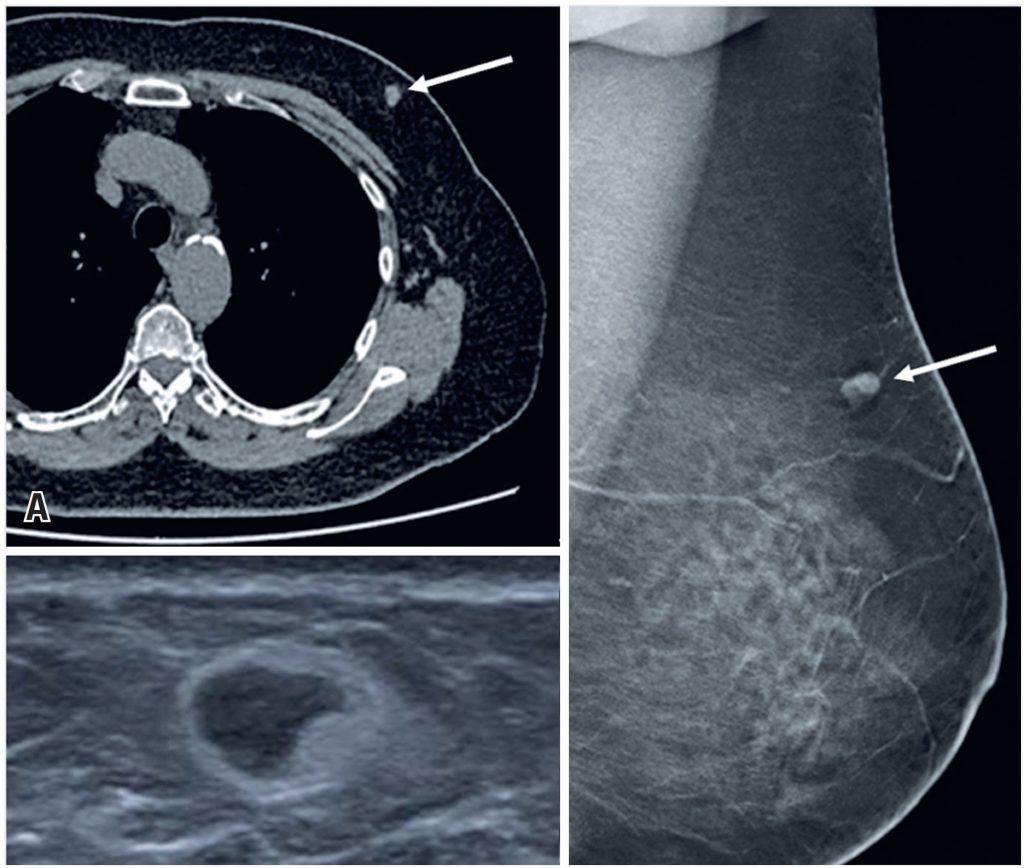

Figure 10

A 68-year-old woman underwent a chest CT for colon tumor staging. (A) The study identified a mass in the union of the upper quadrants of the left breast (arrow). (B) A breast ultrasound revealed an oval-shaped nodule. (C) Mammography showed a nodule suggestive of an atypical intramammary lymph node (arrow). The anatomopathological result was adipose tissue with fibroblastic reaction to hematologic material (hematoma in organization)